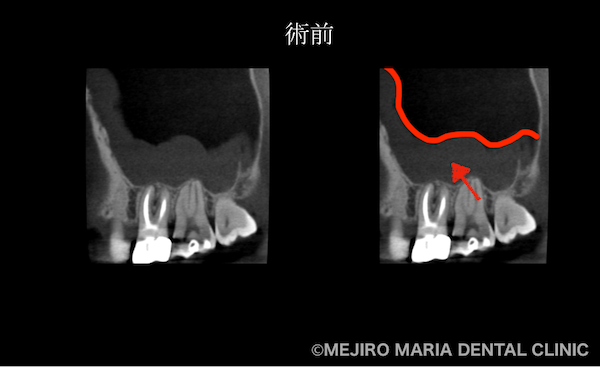

を併発した根尖性歯周炎を、精密根管治療で治癒|術前の歯のCT画像_治療前1.png)

右画像赤矢印部分

患者様によると、1年前に感じた症状は「階段を降りるときに、鋭い歯痛を感じた」とのことで、当時から上顎洞炎(副鼻腔炎)であったことが疑われました。上顎洞炎の場合、時に小臼歯部に、神経を突くような鋭い痛みを覚えることがあります。また、頭痛や頭部を下げるような動作に対する眼下の違和感などが主な症状です。

患者様ご自身は、1年前に根管治療を行った右上4番の歯の予後不良を疑っていました。しかし当院の診査にて、患者様の訴える症状の原因は、数年前に根管治療を行った右上6番の歯の予後不良による根尖性歯周炎と診断しました。

上顎洞炎は、歯性上顎洞炎と鼻性上顎洞炎が併発している場合もあります。上顎洞炎が残存する部分に関しては、耳鼻科にて追加で処置を施していただく必要があるため、再度CT撮影を行い、上顎洞炎の有無を確認しました。

その結果、術前に見られた上顎洞に広がる不透過像(グレーの部分※膿)はほぼ消失していることが確認でき、予後は良好であると判断しました。